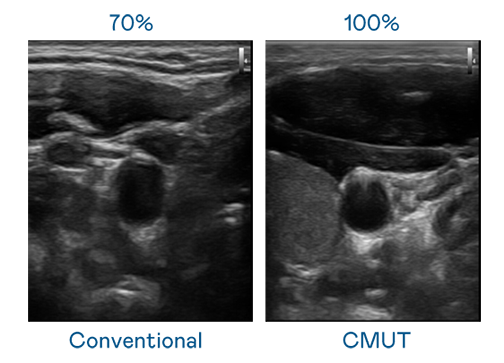

CMUT 技术是一种用电容式微机电元件来产生超音波讯号的技术。与传统 PZT 压电式技术相比,CMUT 频宽增加 30%,更宽频的超音波讯号让影像解析度大幅提升,是实现高影像品质医疗超音波扫描、促进精准医疗发展的关键技术。

超音波影像的解析度高低,首先取决于探头能发出的讯号频宽。yd12399云顶集团 CMUT 可提供高清晰的超音波讯号,提供高频宽、高灵敏度、影像纹理细节更高的超音波影像,协助医护人员缩短影像判读时间及利用精准的医疗影像进行诊断。